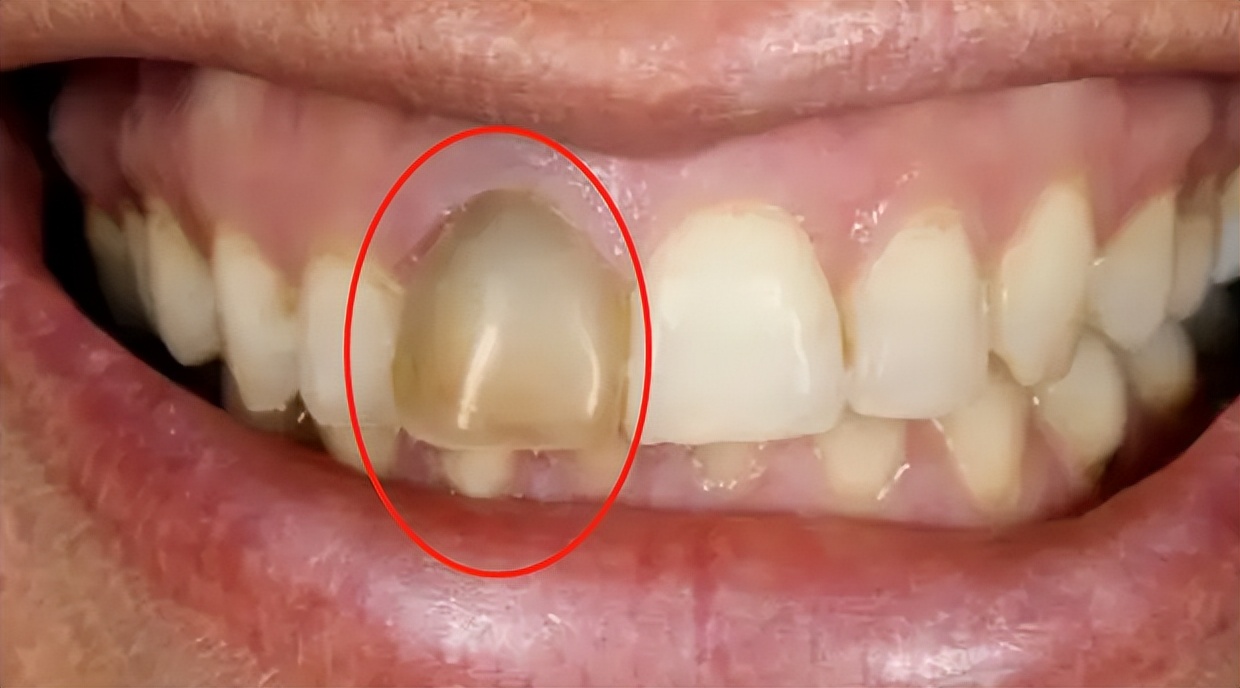

1、通过牙齿颜色判断

一般情况下我们健康的牙齿颜色的是微黄透有光泽的。部分牙髓坏死的牙齿会出现明显的变黑。